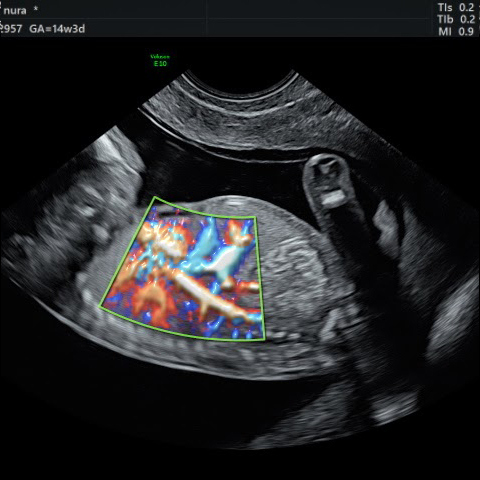

גלריה